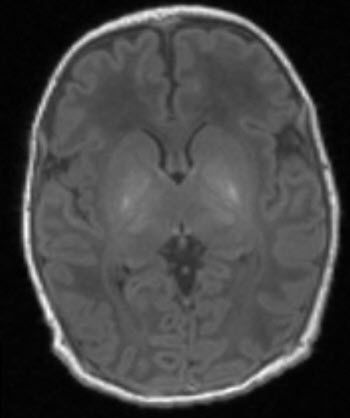

Scan shows that of a baby with brain damageA 15-minute scan could help diagnose brain damage in babies up to two years earlier than current methods.

Any child suspected of having some type of damage is given an MRI scan shortly after birth. This allows doctors to look at black and white pictures of the brain to see if any areas of the brain look lighter than others, as this may suggest damage. Doctors then use this information to give parents an estimation of the extent of the damage, and the possible long-term disabilities their child may face.

In the new study, led by Imperial College London, scientists used MR spectroscopy to assess the health of brain cells in an area called the thalamus, which coordinates a number of functions including movement, and is usually most damaged by oxygen deprivation.